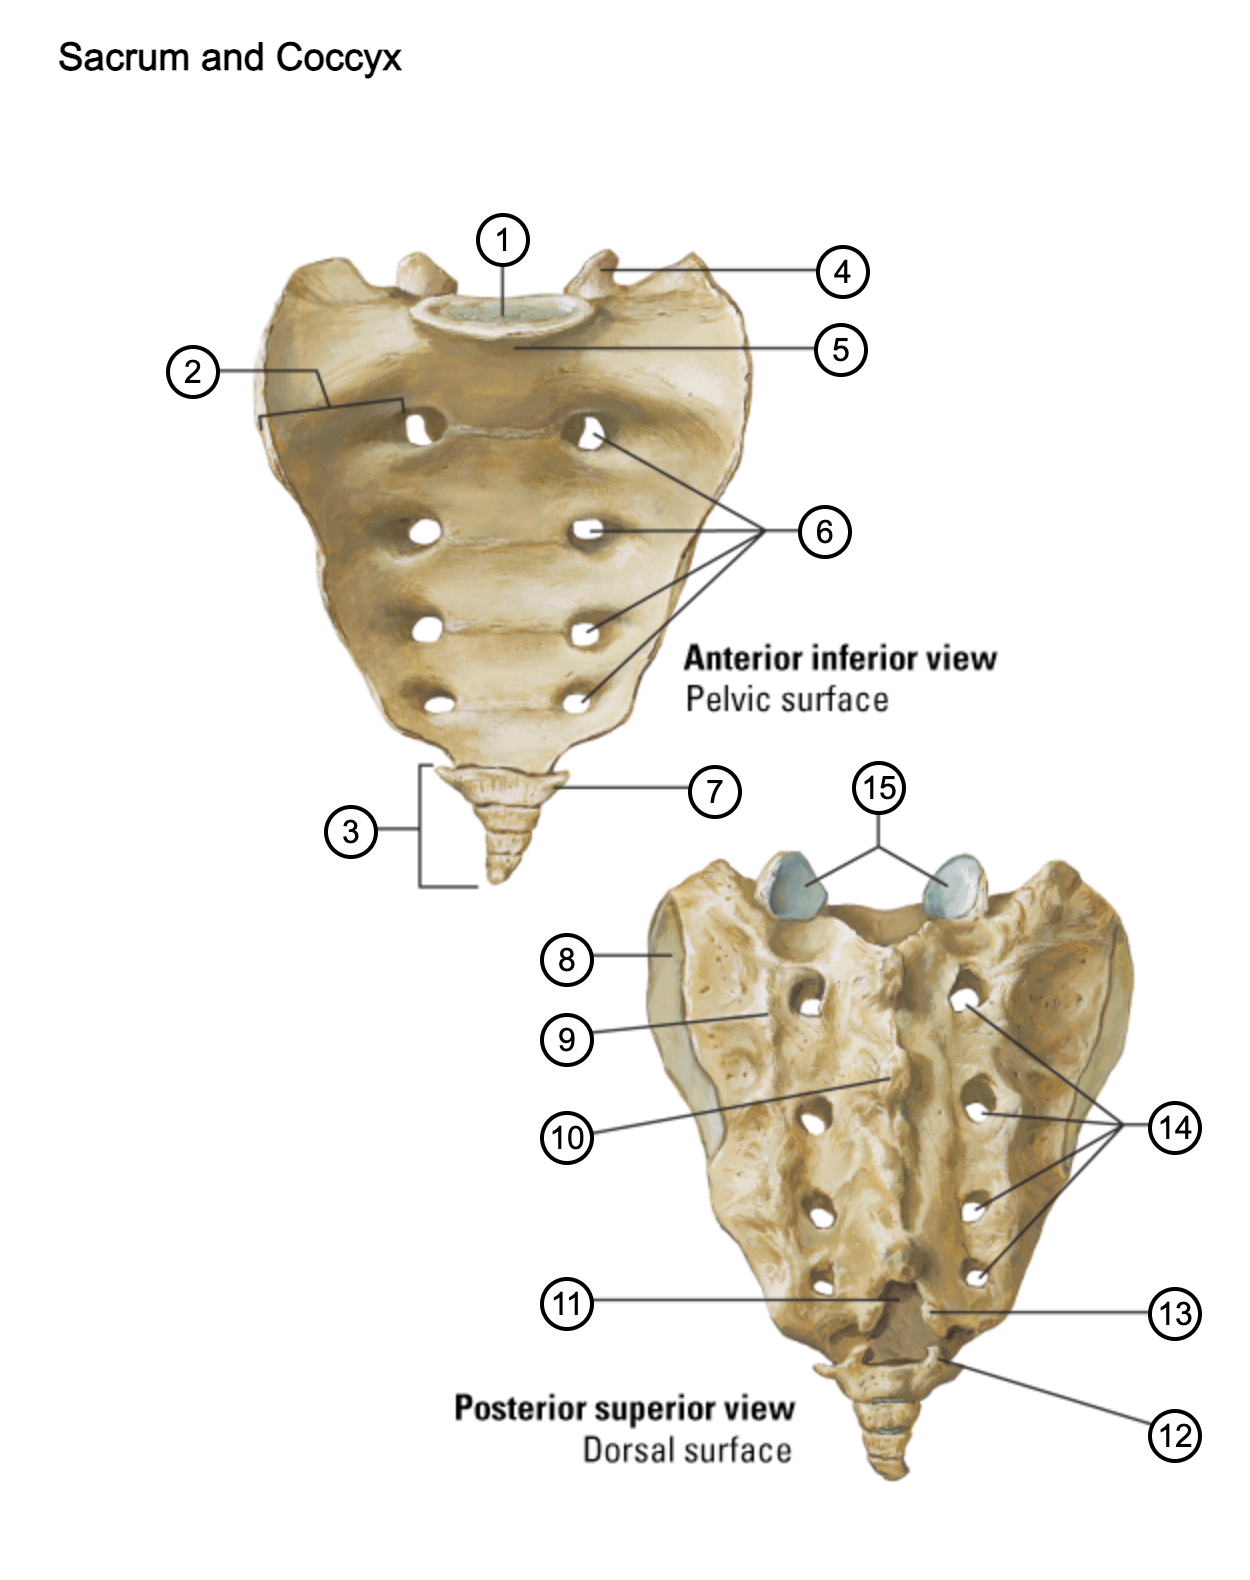

1

lumbosacral articular surface

2

ala of sacrum

3

coccyx

4

superior articular process

5

promontory

6

anterior sacral foramina

7

transverse process of coccyx

8

auricular surface

9

lateral sacral crest

10

median sacral crest

11

sacral hiatus

12

coccygeal horn

13

sacral horn

14

posterior sacral foramina

15

facets of superior articular processes